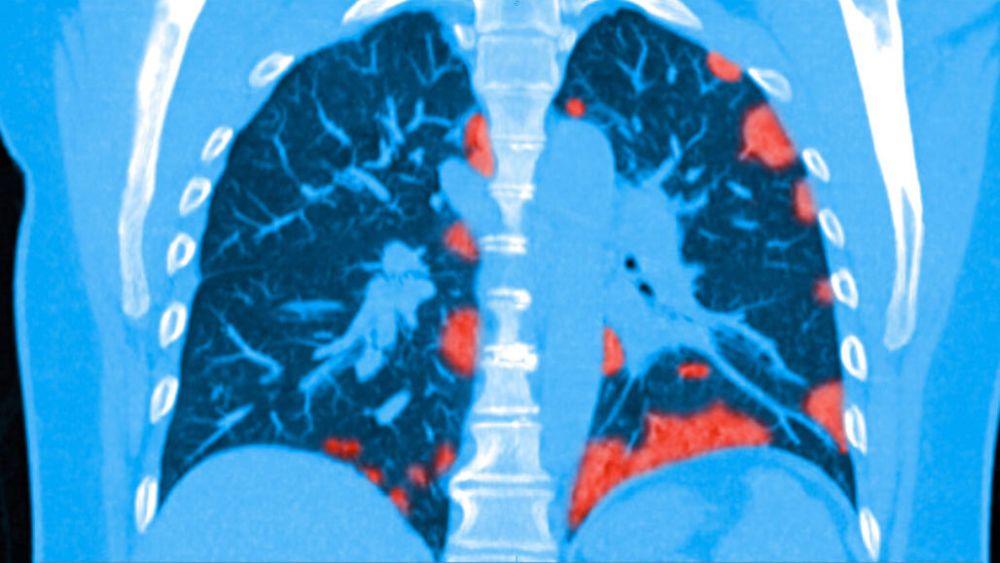

Nejčastěji u nich vidíme poruchy plicní difuze a poruchu okysličení krve zejména při zátěži. Zajímavé je, že se vyskytují i lidé, u nichž se na CT plic objeví fibrotické změny, a oni nepociťují, že by se jim hůře dýchalo.

Jde o soubor příznaků a chorobných změn, které postihují nejen plíce, ale i řadu jiných orgánů a tkání. Jedná se o změny způsobené:

– hypoxemií (nízkým obsahem kyslíku v krvi), zejména hypoxií (nedostatku kyslíku) v orgánech a tkáních při covid pneumonii a syndromu akutní dechové tísně

– zánětlivou a koagulační (srážecí) fází akutního covid a post-akutního covid

– přímým účinkem viru

– intenzivní péčí